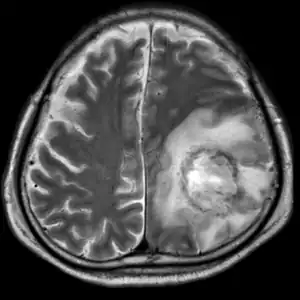

| T2-weighted MRI showing liquefied, necrotic brain tissue as a result of GAE caused by an infection of Acanthamoeba, genotype T18 | |

A: T2-weighted MRI showing liquefied, necrotic brain tissue as a result of GAE caused by Balamuthia mandrillaris